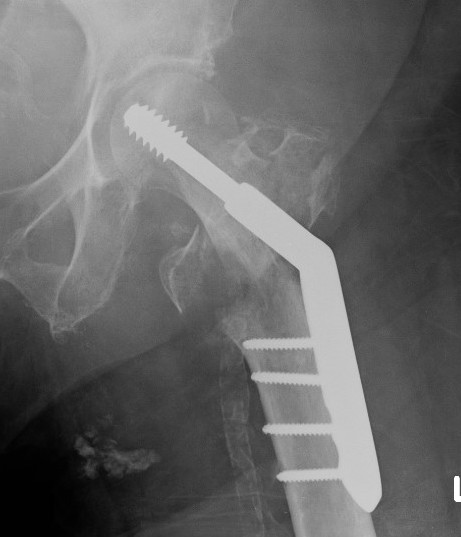

Dynamic hip screw

Mechanism

Plate is a lateral tension band whilst the sliding screw allows controlled fracture impaction

Technique

- traction table with anatomic reduction

- traction, adduction, internal rotation

Lateral approach to femur

- elevate vastus lateralis and control bleeding from perforators

Guide wire

- centred in femoral head in 2 planes

- tip-apex distance < 25 mm

Tip - apex distance

- from tip of screw to apex femoral head

- accumulative on AP and lateral

- > 25 mm, increases cut out

Measure angle

- wire in centre of neck / centre of head

- usually 130o prosthesis

Ream to within 5 mm of end of wire

- tap

- insert screw / tip apex distance < 25 mm

- attach plate

b. Trochanteric stabilization plate

Theory

- buttresses the GT and prevents lateral displacement